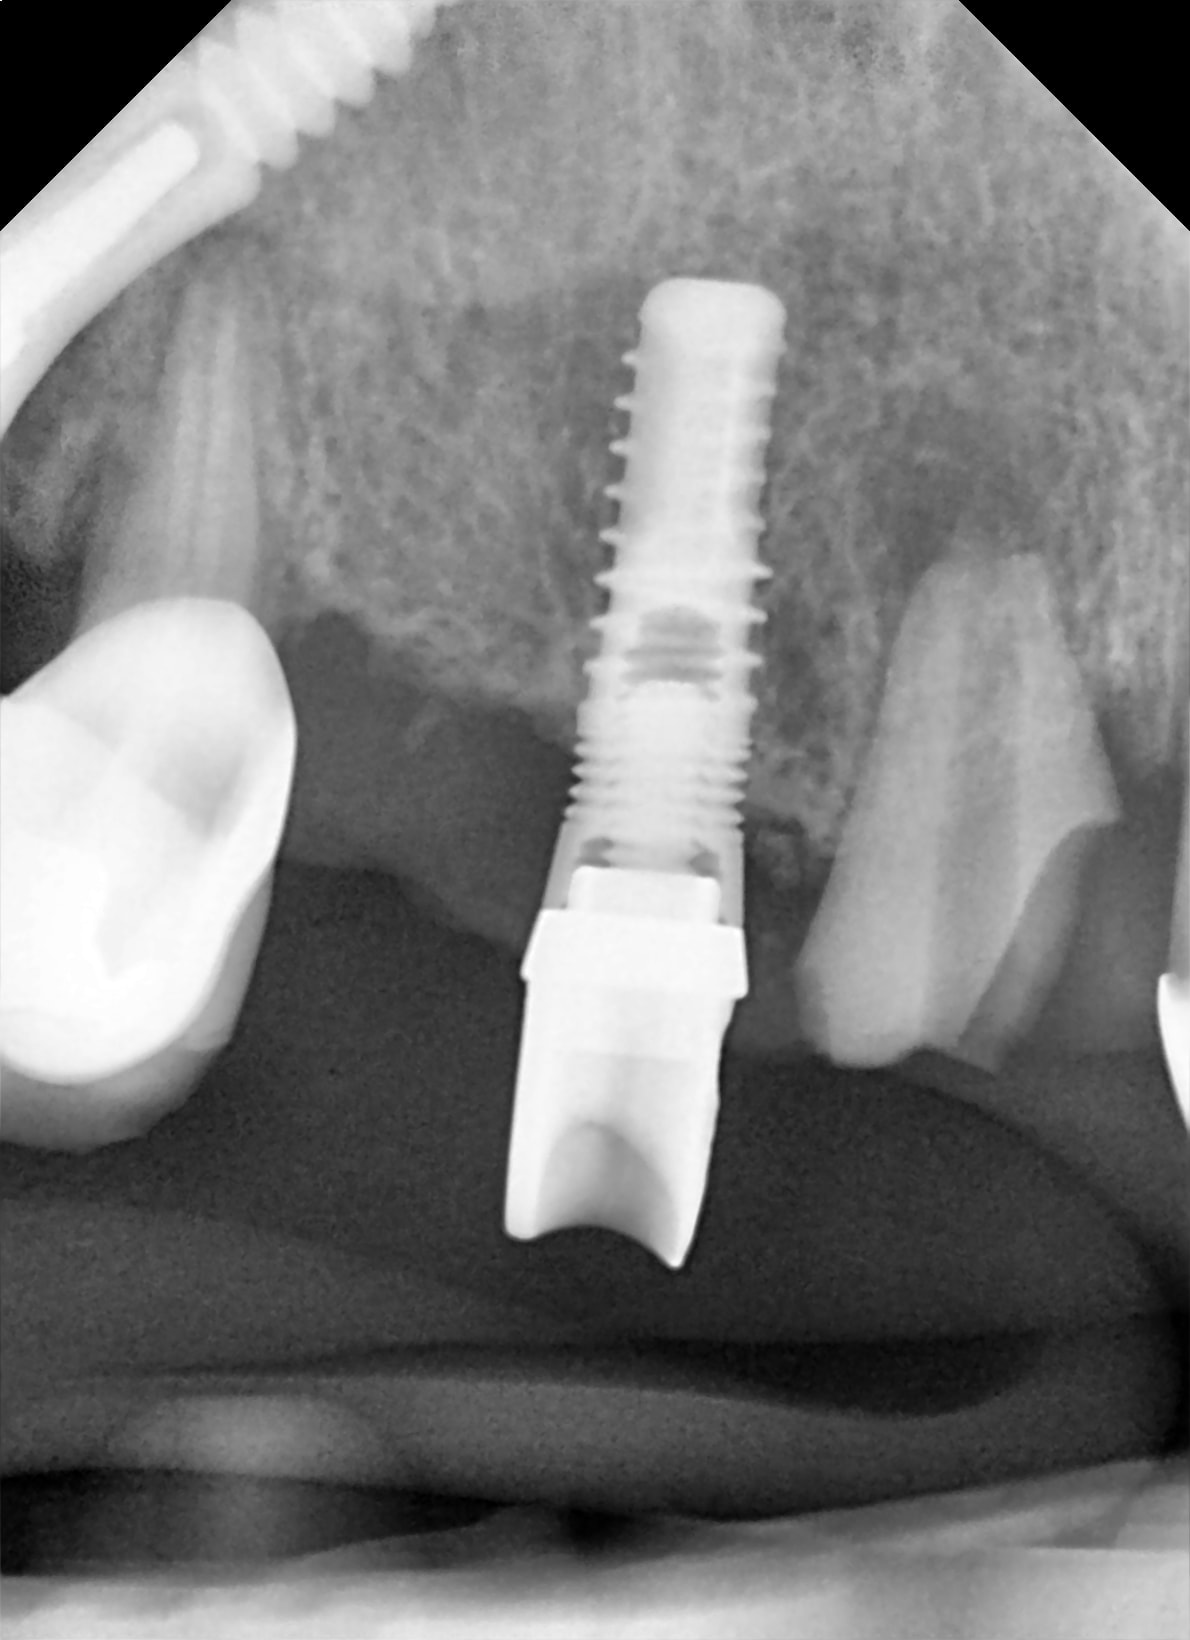

SVP, aidez moia identifier cet implant parce'que je n'arrive pa a le retrouver sur whatimplantsisthat ou osseosource...or peut etre je suis trop fatigue!

j'hésite...entre un vieux serf EVL ou un tekka progress...

j'hésite car les microspires au col correspondrait plus au progress...mais l'apex plat plus à l'EVL...

Apres avoir etudie les radios de Global D je pense que c'est ca:

Implant EVL® S Global D.

Autres idees?

peut être de vieux microvent zimmer....c'est ce qui me vient et correspond le mieux à ce que je peux voir....

http://osseosource.com/dental-implants/product_info.php?manufacturers_id=27&products_id=1361

le premier c'est EVL de serf /global D

les seconds ça ressemble a IDI CAM

http://www.idi-dental.com/fr/produit/idcam-m

c'est une possibilité avec le microvent...

mais pour pouvoir être sûr...faut de meilleurs clichés...et pas des vignettes type timbre poste tellement compressés qu'il n'y a plus d'infos vraiment exploitables...